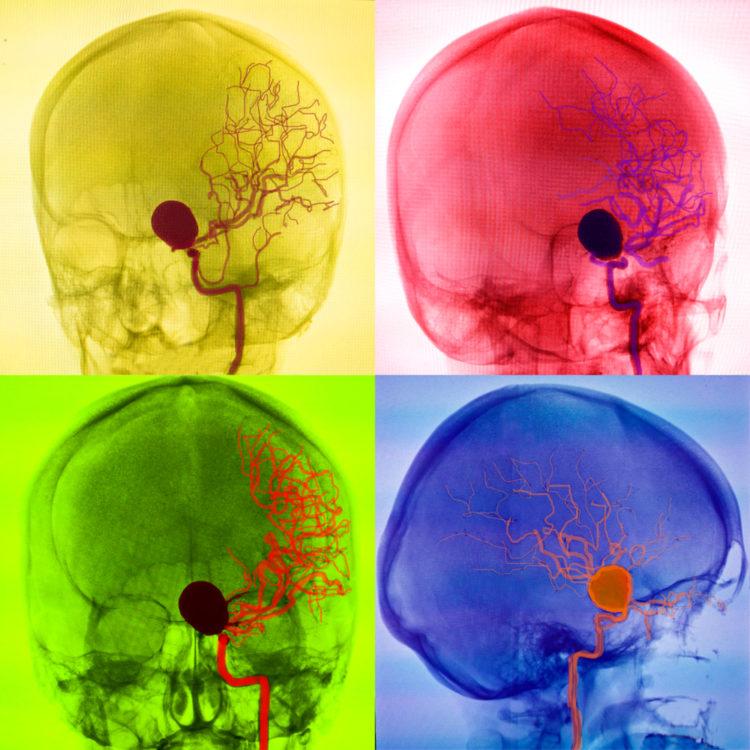

Chụp mạch máu não là một xét nghiệm được dùng để quan sát xem các mạch máu cung cấp máu ở đầu và cổ cung cấp máu cho não có bị hẹp hay tắc nghẽn không. Những bất thường hẹp hay tắc nghẽn này có thể gây ra bệnh đột quỵ hoặc bệnh phình động mạch.

Trong quá trình làm xét nghiệm, bác sĩ thường dùng một ống thông dài và dẻo để luồn nó tới các mạch máu ở đầu và cổ. Sau đó, thuốc cản quang sẽ được bơm vào mạch máu qua ống thông này. Nhờ có thuốc cản quang, hình ảnh của các động mạch sẽ được làm nổi rõ lên và hiển thị rất chi tiết trong phim chụp x-quang. Từ đó, bác sĩ có thể xác định được động mạch nào bị hẹp.

Chụp mạch máu não (chụp mạch máu não) được sử dụng để đánh giá tình trạng các tĩnh mạch hoặc bốn động mạch lớn có chức năng đưa máu lên não.